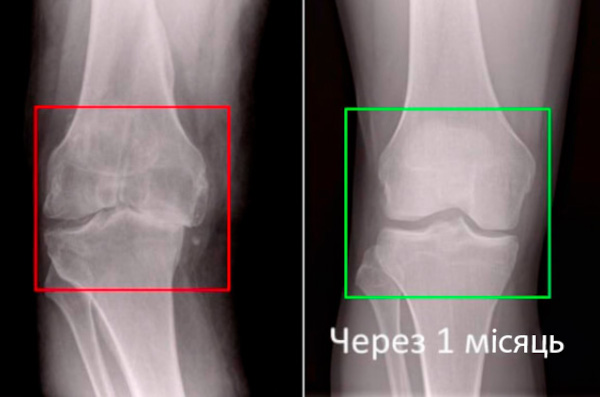

Зубицька: "Я говорю про спеціальний засіб «Пантогор». Це засіб, який дозволяє в найкоротші терміни, буквально від 14-ти днів, забути про біль в спині і суглобах, і протягом двох місяців вилікувати навіть дуже складні випадки.

Зубицька: "Це означає, що середньовічна медицина йде в минуле і ви зможете вилікувати свої захворювання в домашніх умовах за місяць-два. «Пантогор» не заморожує, не знеболює, він "перезапускає ". Усуває причину смого болю і повертає суглоби, хребет в нормальний стан. Хворий не просто позбавляється симптомів, а вирішує основну проблему - ослаблене повільними, старими клітинами, кровопостачання хрящів.

Мені 42 роки. Кілька років тому у мене був важкий грип, після якого я загриміла в лікарню з ускладненнями. Одним з ускладнень став запальний процес в суглобах, особливо в колінному. Рентген показав початкові ознаки артрозу колінного суглобу. А мені на той момент було 39 років. При ходьбі коліно клацало, скрипіло, при підйомі по сходах виникали хворобливі відчуття. Я перепробувала багато: щось допомагало більше, щось менше. Але тільки «Пантогор» задовольнив всі мої вимоги. Йому вдалося прибрати і клацання, і біль. Останнє УЗД нічого не показало. Так і хочеться помахати цим УЗД перед лікарями, які говорили, що гірше може бути, а краще вже не стане. Гель тримаю під рукою і всім рекомендую. Мене він врятував, це точно.